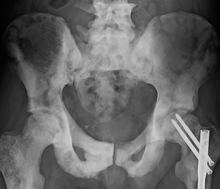

Surgery[edit | edit source]

Radical prostatectomy is considered the mainstay of surgical treatment of prostate cancer, where the surgeon removes the prostate, seminal vesicles, and surrounding lymph nodes. It can be done by an open technique (a skin incision at the lower abdomen), or laparoscopically. Radical retropubic prostatectomy is the most commonly used open surgical technique.[citation needed] Robotic-assisted prostatectomy has become common.[151] Men with localized prostate cancer, having laparoscopic radical prostatectomy or robotic-assisted radical prostatectomy, might have shorter stays in the hospital and get fewer blood transfusions than men undergoing open radical prostatectomy.[152] How these treatments compare with regards to overall survival or recurrence-free survival is unknown.[152]

Transurethral resection of the prostate is the standard surgical treatment for benign enlargement of the prostate.[151] In prostate cancer, this procedure can be used to relieve symptoms of urinary retention caused by a large prostate tumor, but it is not used to treat the cancer itself. The procedure is done under spinal anesthesia, a resectoscope is inserted inside the penis and the extra prostatic tissue is cut to clear the way for the urine to pass.